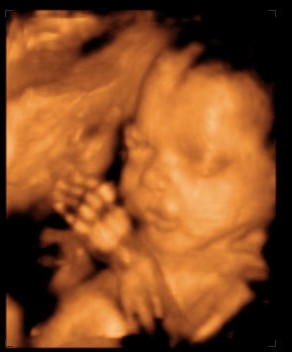

Érdekesség ként:ime egy pár kép a bébinkről. Mert úgye elmentünk Dunakeszi Kenguruba 4D felvételre...ésssss.nem bántuk meg. A csajszikánkba már most szerelmes vagyok: és hát apja lánya, talán az orrocskája az enyém.

25+2 Kép Kép